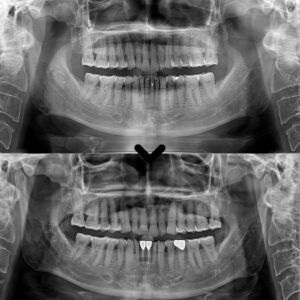

성남치과 남편 소개로 왔어요. 골다공증 환자분 뼈이식을 포함한 어금니 무절개 임플란트 사례

성남치과 남편 소개로 왔어요. 골다공증 환자분 뼈이식을 포함한 어금니 무절개 임플란트 사례 안녕하세요. 성남치과 서울박사치과입니다. 골다공증은 뼈의 밀도가 감소하고 뼈가 약해지는 질환으로, 주로 노년층에서 발생합니다. 이로 인해…